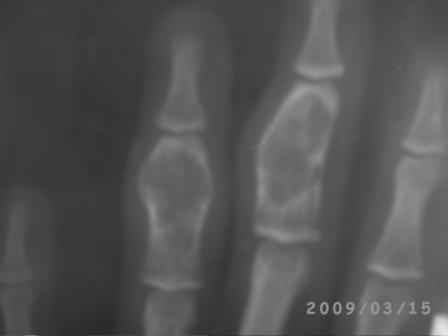

Re: Непонятный процесс в основной фаланге пальца

Уважаемый Юрий, действительно, онкологи делали пункционную биопсию.

Конечно, мы во время операции будем брать материал на гистологию, а также удаление очага и замещение аутотрансплантатом тоже в плане рассматривается, как на примере, которая была представлена на форуме. правда снимки не очень качественные, прощу извинения!